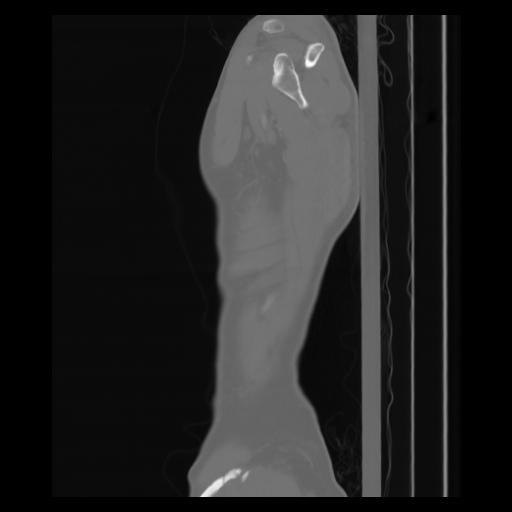

30 CUERPO,CE,Sagittal,3.000,CUERPO,Sagittal,